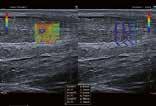

Hochauflösender Ultraschall in der Sportpraxis

Wie kamen Sie zur Sonographie?